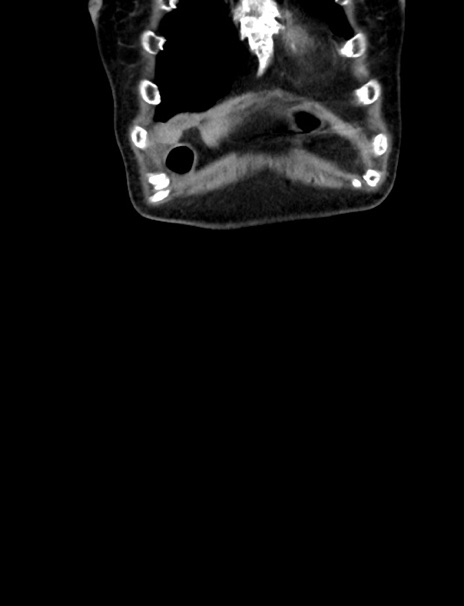

横断像